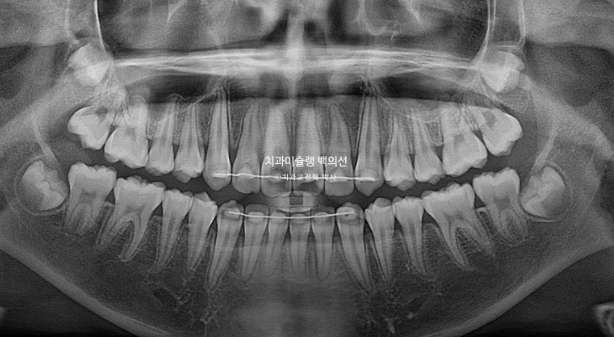

25.07

앞니 치축의 개선은 엑스레이에서 더 정확히 확인이 됩니다.

24.02~25.07